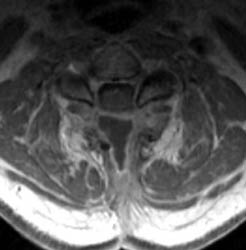

46 y.o. male, initial complaint of progressed with myelopathy,

difficulty walking, and imbalance. Underwent laminectomy C3 to C7, 2 months

prior to these images. Worsening numbness and weakness brought patient to seek

neurosurgical consultation again, prompting repeat imaging.

| Sagittal T1 pre (A) and post contrast

(B), sagittal T2 (C) and Axial T1 post contrast (D) MRI images

of the cervical spine demonstrating a large posterior fluid collection with an

obvious sinus tract inferiorly and associated gas bubbles. This was proved to be

a post-operative seroma and epidural scar (note the thick rind of enhancement)

that was partially accounting for this patient's residual and worsening symptoms

despite the initial decompressive surgery. |